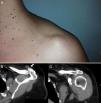

The patient was a 40-year-old woman. She came to the clinic due to the appearance of a tumor in the acromioclavicular joint (ACJ) after a vertical traction effort with the left arm (lifted, from the ground, a load of 40kg) 2 days prior. The lesion was painless, rounded and slightly compressible. It showed no inflammatory signs. There was no functional limitation of the shoulder but noticeable discomfort upon compressing the lesion (Fig. 1A).

Scanning with simple X-rays identified cortical irregularities on both sides of the ACJ. An ultrasound showed integrity of the rotator cuff and subacromial structures, with no alterations of the subacromial or subdeltoid bursae. There was acromioclavicular capsule distension and cortical marginal proliferation. The tumor was seen as a structure of defined edges, measuring 22mm×13mm and homogeneous anechoic content, compressible upon pressure. No continuity between the tumor and the joint capsule was found. A computed tomography (CT) described the injury as a rounded cystic structure dependent on the dorsal joint capsule which protruded cephalad (Fig. 1B and C).